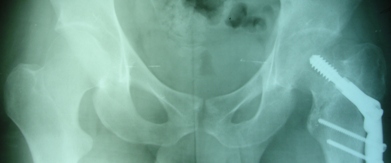

Уважаемые коллеги, приношу извинения за перерыв в работе -

был в командировке. За это время больному сделали КТ и,  сегодня,

снимки. Укорочение конечности - 1-1,5 см, ШДУ-115 градусов, замедленная консолидация,

остеопороз.

Вопрос о тактике дальнейшего ведения пациента (напоминаю, возраст 19

лет)?